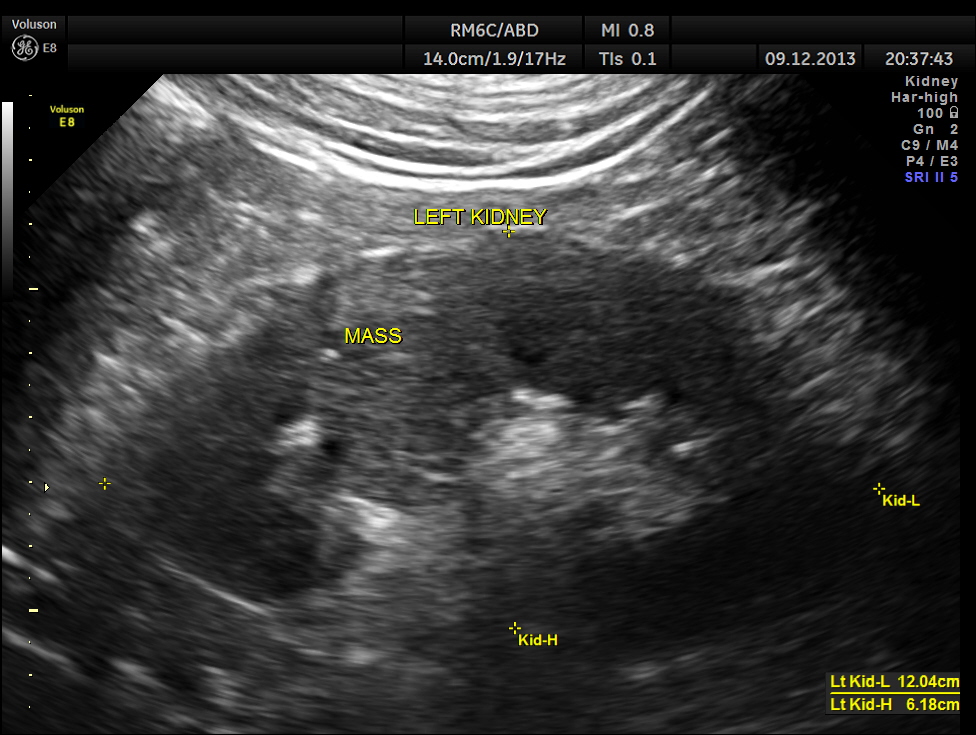

The pictures of the left kidney are given below. An echogenic mass lesion is seen .

Regular power doppler appears unremarkable.

The findings were confirmed with CT Scan . he underwent radical left nephrectomy and the biopsy was reported as RENAL CELL CARCINOMA.

The images presented above show certain features better seen with reconstruction . But the diagnosis as is usual is made out with the 2 D images .